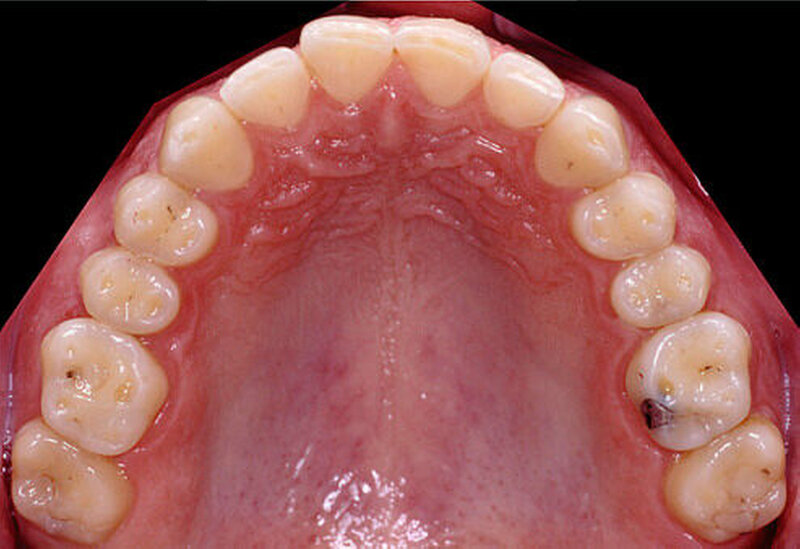

Wurde die provisorische Restauration funktionell und ästhetisch vom Patienten akzeptiert, kann mit der definitiven Versorgung begonnen werden. Es bietet sich eine quadrantenweise Präparation und Kieferrelationsbestimmung an, wobei die vertikale und die horizontale Kieferrelation nicht mehr ver-ändert werden. Die definitive Versorgung, zum Beispiel mit glaskeramischen Einzelzahnrestaurationen, kann konventionell mit der Presstechnik oder mit der CAD/CAM-Technik erfolgen. Im Idealfall könnten bei der CAD/CAM-Technik die Datensätze der langzeitprovisorischen Onlays für die Konstruktion der vollkeramischen Kauflächen verwendet werden.

Für die Umsetzung in die definitiven Kauflächen-Veneers bieten sich folgende Materialien an: Presskeramik (IPS e.max Press, IPS Empress Esthetic) oder die CAD/CAM-Fertigung mit vorkristallisierten Blöcken (IPS e.max CAD). Aufgrund der hohen Belastung im Kauflächenbereich sollte im Seitenzahnbereich monolithischen Lithiumdisilikat(LS2)-Restaurationen der Vorzug gegeben werden (Abbildung 5) [Güß, 2010]. Bei der Präparation ist zu beachten, dass der adhäsive Verbund zum Zahnschmelz als besser einzustufen ist als zum Dentin. Gleichzeitig stabilisiert das im Vergleich zum Dentin höhere Elastizitäts-Modul des Zahnschmelzes die Keramik. Im Zweifelsfall sollte daher vorzugsweise Schmelz erhalten und stattdessen eine geringere Keramikschichtstärke realisiert werden. Falls erforderlich, wird die Okklusalfläche mit einem Finierdiamanten (25 bis 40 µm Korn) geringfügig abgetragen; unter okklusalen Kontaktpunkten maximal 1,5 mm unter Berücksichtigung der dynamischen Okklusion. Die Präparationstiefe sollte auf die durch einen Silikonschlüssel oder eine Tiefziehfolie darstellbare Außenkontur der definitiven Restauration (Wax-up) ausgerichtet sein und kontrolliert werden. Ein zirkulärer Stützrand ist nicht erforderlich; die Präparationsgrenze sollte jedoch nach Möglichkeit vorhandene Füllungskavitäten überdecken [Edelhoff et al., 2013; Kern et al., 2012}. Die okklusale Schichtstärke von Polymer- und Keramikonlays konnte in einer In-vitro-Untersuchung bis zu 0,3 mm reduziert werden [Schäfer, 2014]. Hinsichtlich der klinischen Bewährung vollkeramischer Kauflächen-Veneers ist die Datenlage zurzeit noch unzureichend. Für monolithische Kauflächen-Veneers aus Lithiumdisilikat bestehen auf Molaren günstige Prognosen [Clausen et al., 2010].